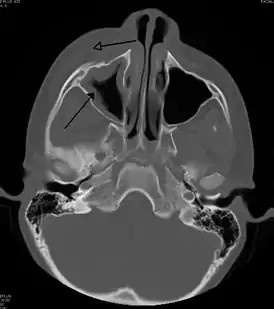

Периорбитальный целлюлит необходимо дифференцировать от орбитального целлюлита, который является чрезвычайной ситуацией и требует внутривенного введения (IV) антибиотиков. В отличие от орбитального целлюлита, у пациентов с периорбитальным целлюлитом отсутствуют выпуклые глаза (экзофтальм), ограниченное движение глаз (офтальмоплегия), боль при движении глаз, или потеря зрения. Если какой-либо из этих признаков присутствует, надо полагать, что пациент имеет орбитальный целлюлит и начать лечение IV антибиотиками. КТ-сканирование может быть сделано, чтобы очертить расширение инфекции.